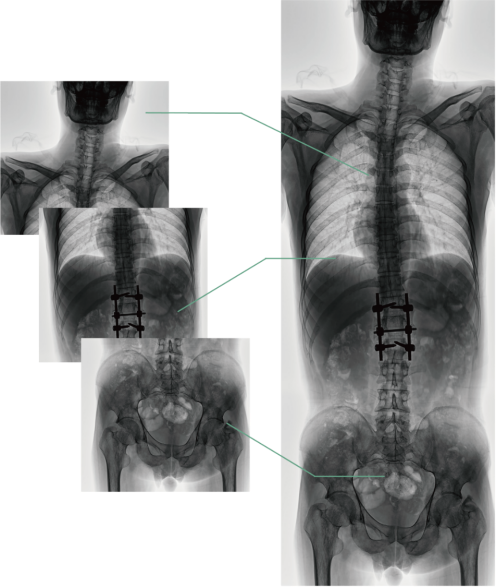

四、圖像自動拼接

圖像自動拼接功能實現全脊柱、全下肢全景攝影,解決在觀察頸椎至尾椎的脊柱側彎或其他病變時不能一次成像的問題,能夠直觀的顯示脊柱和下肢的整體解剖形態(tài)及側凸部位。